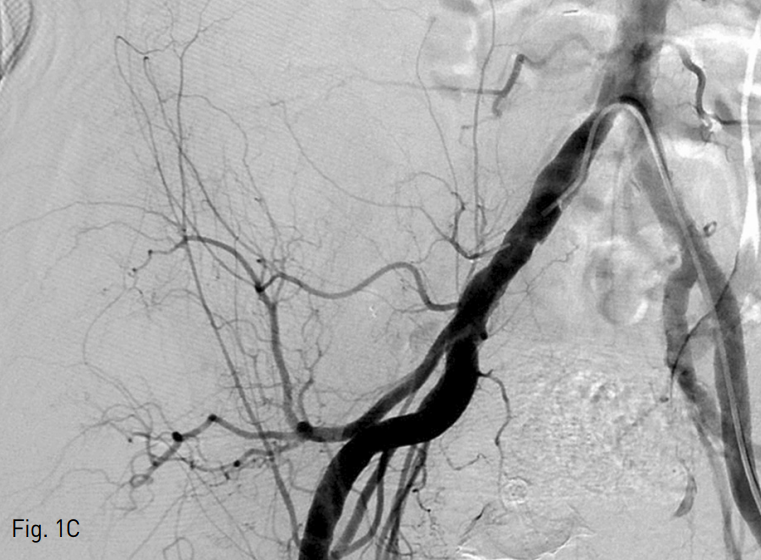

Fig. 1. A 75-year-old man with Jackson-Pratt catheter tract bleeding after radical excision of right kidney.

C. A common iliac arteriogram showed no clear sign of bleeding.